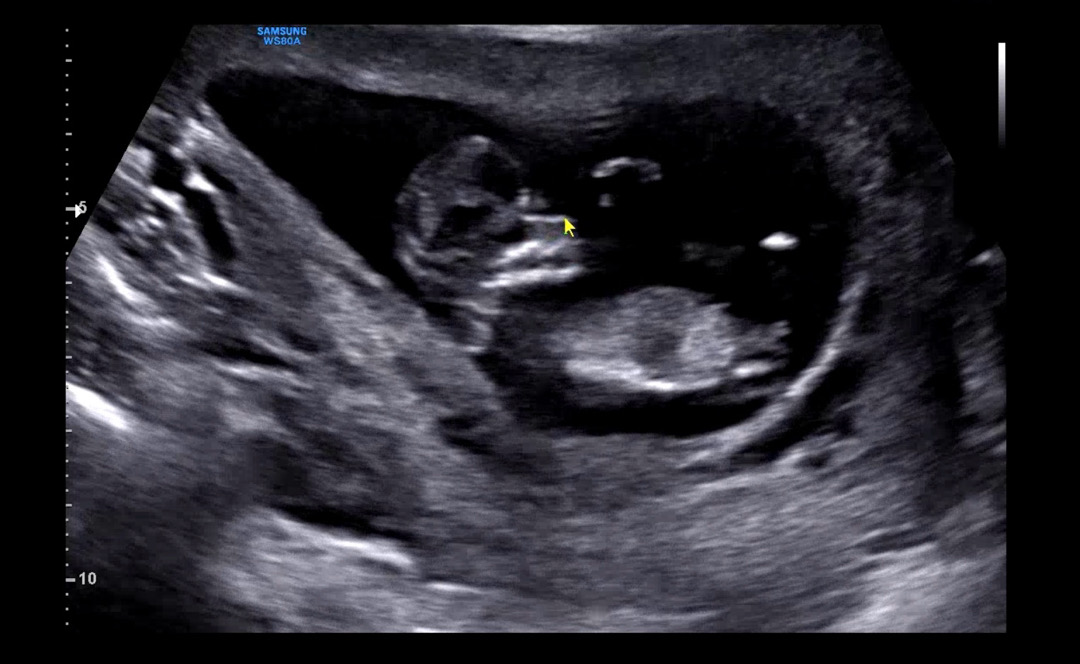

12주2일 각도법 ㅜㅜㅜ궁금해여 ㅠㅠ

고수님들 보시기에 어떠신가용?? ㅜㅜㅠㅠㅠ 생식기는 딱 보이는거같은데….. ㅜㅜㅜㅜ